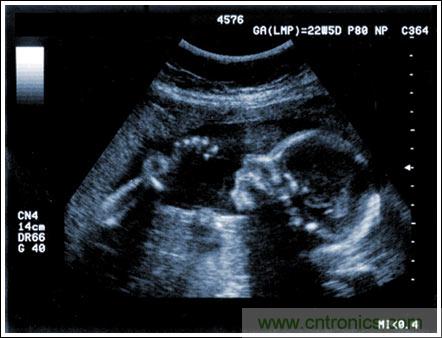

超聲成像系統(tǒng)及主要子功能電子元件的設(shè)計(jì)考慮

【導(dǎo)讀】該應(yīng)用筆記介紹了超聲成像系統(tǒng)的設(shè)計(jì)考慮,討論成像系統(tǒng)的小型化、低成本和便攜化的發(fā)展趨勢(shì),同時(shí)闡述了在小型系統(tǒng)中實(shí)現(xiàn)大型車載系統(tǒng)所具備的性能和診斷能力的重要條件。文章探討了超聲系統(tǒng)的子功能以及對(duì)電子元件的要求,重點(diǎn)討論了傳感器、高壓復(fù)用器、高壓發(fā)射機(jī)、成像通道接收機(jī)、數(shù)字波束成形、波束成形數(shù)字信號(hào)處理及顯示處理等。

通過發(fā)射超聲能量進(jìn)入人體,接收并處理返回的反射信號(hào),相控陣超聲系統(tǒng)可以生成體內(nèi)器官和結(jié)構(gòu)的圖像,映射血液流動(dòng)和組織運(yùn)動(dòng),同時(shí)提供高準(zhǔn)確度的血流速度信息。傳統(tǒng)設(shè)計(jì)中,構(gòu)建這樣的成像系統(tǒng)需要大量的高性能相控陣發(fā)射器和接收器,使得車載設(shè)備體積龐大且價(jià)格昂貴。近年來,隨著集成工藝的進(jìn)步,設(shè)計(jì)人員能夠獲得小尺寸、低成本而且高度便攜的成像系統(tǒng)方案,并可達(dá)到接近大型成像設(shè)備的性能指標(biāo)。而新的設(shè)計(jì)挑戰(zhàn)依然存在,即在進(jìn)一步提高方案集成度的同時(shí)提高系統(tǒng)性能和診斷能力。